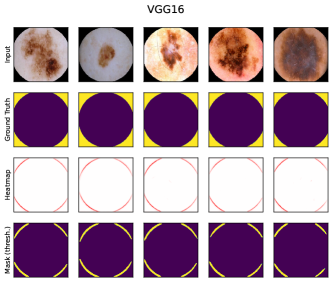

6.4 Spatial Bias Localization

To spatially localize biases in input space with CAVs, we compute local explanations for the element-wise product of latent activations and concept direction (see Eq. 2). We use the controlled artifacts, specifically timestamp (HyperKvasir) and micropscope (ISIC2019) with ground truth concept localization masks for evaluation. We compute (1) the percentage of relevance within the ground truth mask and (2) the Jaccard index, or Intersection over Union (IoU), of the binarized localization mask with the ground truth. In Fig. 9, we report both metrics using CAVs computed on different layers of VGG16 and ResNet50. The layer choice for concept representations is key, as for example middle layers perform better to localize timestamps and earlier layers are more effective to localize the microscope. In comparison with Fig.7, we find that the optimal layer for bias localization may differ from the one for sample retrieval. Interestingly, the IoU for the microscope artifact is consistently low, as models primarily focus on the border of the circle instead of the entire area, as indicated by qualitative results in Appendix A.6.3. Unlike artifact relevance, the IoU metric also measures how much of the expected areas the computed mask does not cover.